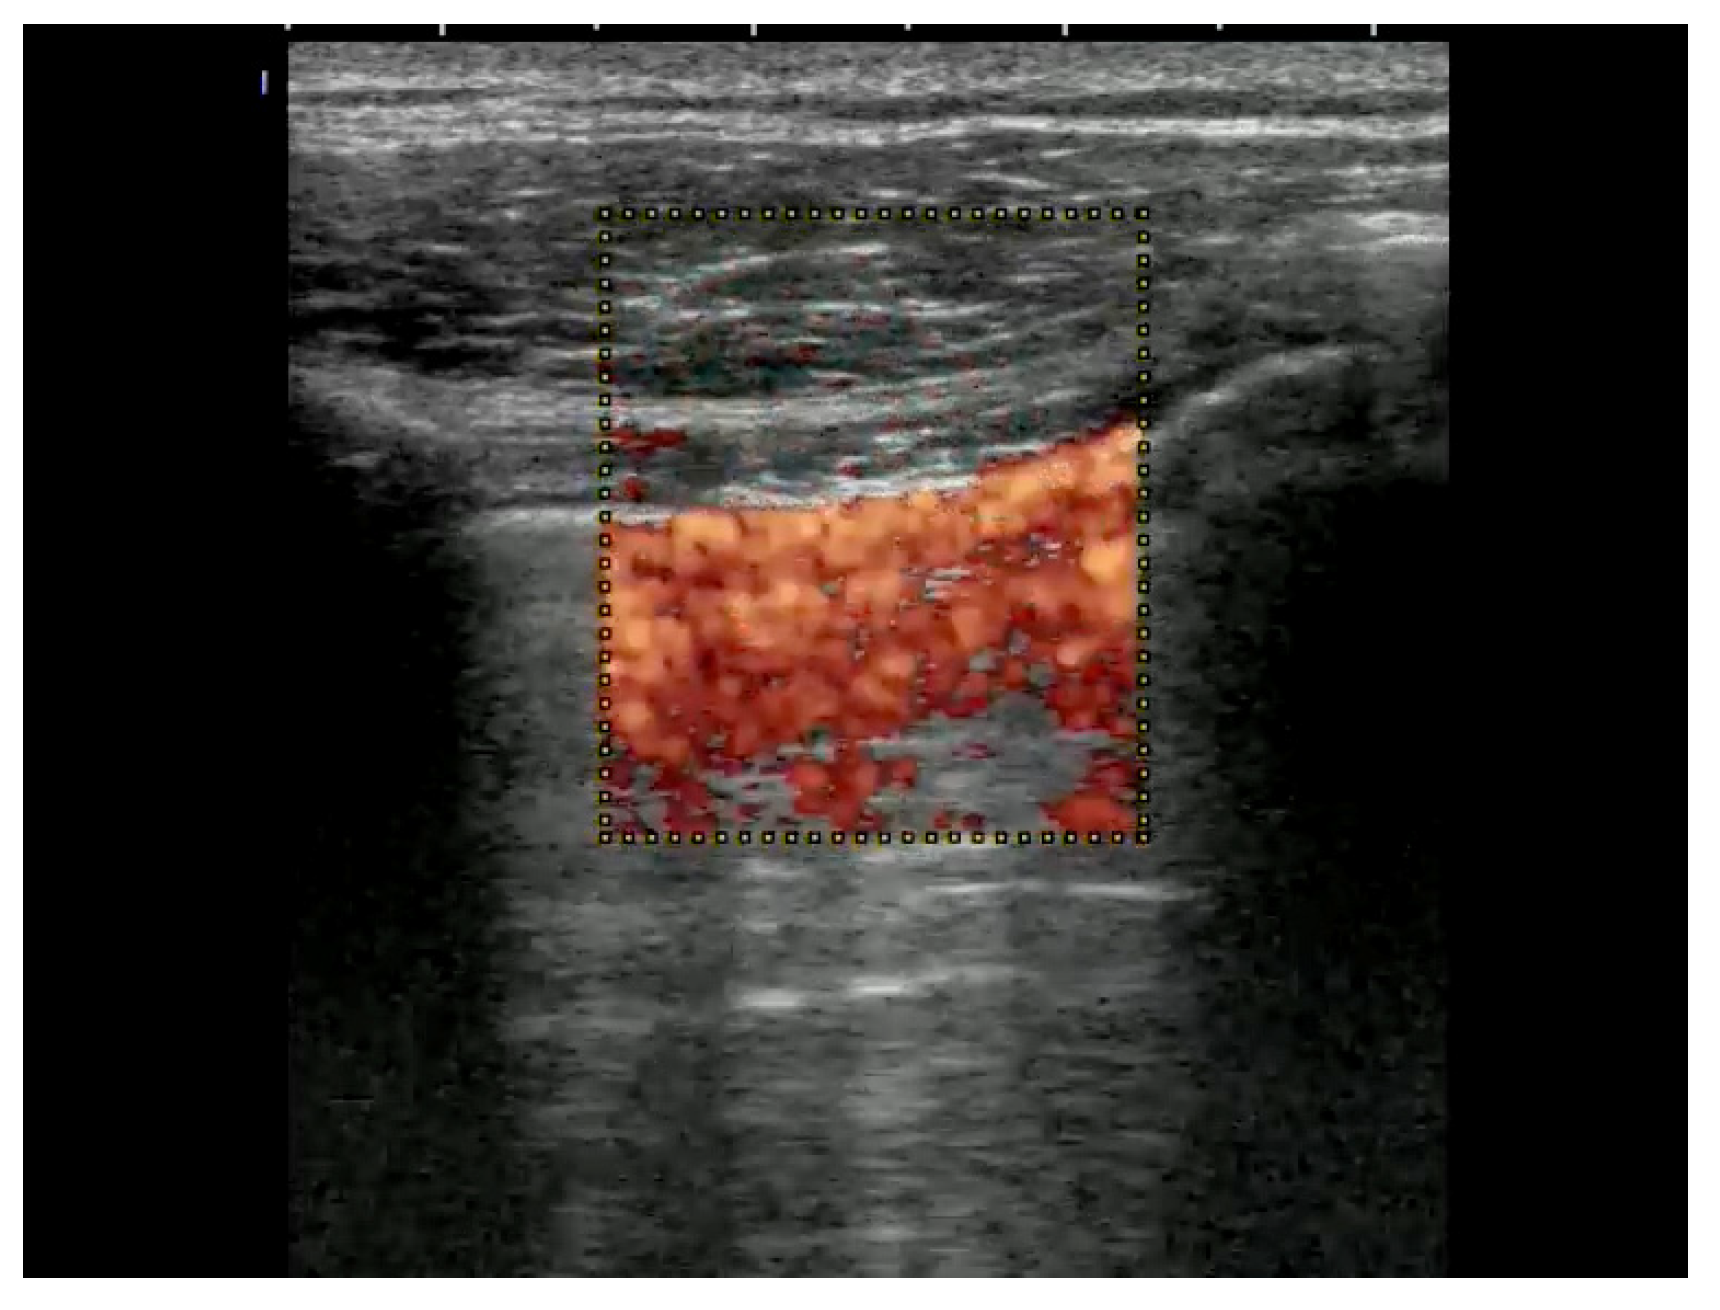

7.4.3. Deep Vein Thrombosis

An examination of the veins is usually performed with a linear transducer. Deep vein thrombosis is most reliably detected through compression sonography, although it may be obvious as an echogenic entity within the vessel lumen in some cases. The probe is in a transverse orientation with respect to the vessel. With pressure in a perpendicular vector on the vein, the vessel should collapse completely. It is important in this clinical situation to decide if there is a central pulmonary embolism too. In a peri-arrest situation, it is enough to apply a two-point compression ultrasound (inguinal and popliteal). Color Doppler is rarely required and would only be used to identify the location of vessels, as the examination relies solely on venous compression [] (Figure 19). Possible additional signs in deep vein thrombosis can be found by looking for signs of central pulmonary embolism.

Figure 19.

In the popliteal 4-region, the popliteal vein and the saphena parva vein cannot be compressed due to a thrombus.